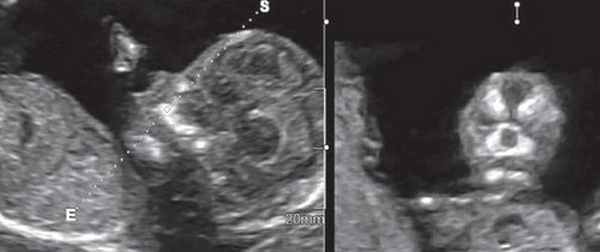

3D/4D объемная визуализация

Использование трехмерного ультразвука, включая визуализацию поверхности, многоплоскостное и многослойное изображение, позволяет точно оценить различные черепно-лицевые структуры и их аномалии, включая расщелину неба (рис. 15, 16) и краниосиностоз. Изображения могут быть полезны для консультирования (рис. 17, 18). Использование 3D (рис. 19) может помочь дифференцировать закрытые и открытые швы. Использование 4D может быть использовано для оценки выражений лица.

Рисунок 15: Плод второго триместра с двусторонней расщелиной губы и неба. 3D аксиальный вид показывает потерю целостности (стрелки) губы (L) и неба (P) с обеих сторон.

Рисунок 16: Плод второго триместра с расщелиной губы и неба по средней линии. 3D аксиальный вид показывает потерю целостности (стрелки) губы (L) и неба (P) по средней линии. Цветные рамки справа показывают ориентацию активных изображений слева: аксиальный вид (1), сагиттальный вид (2) и венечный вид (3).